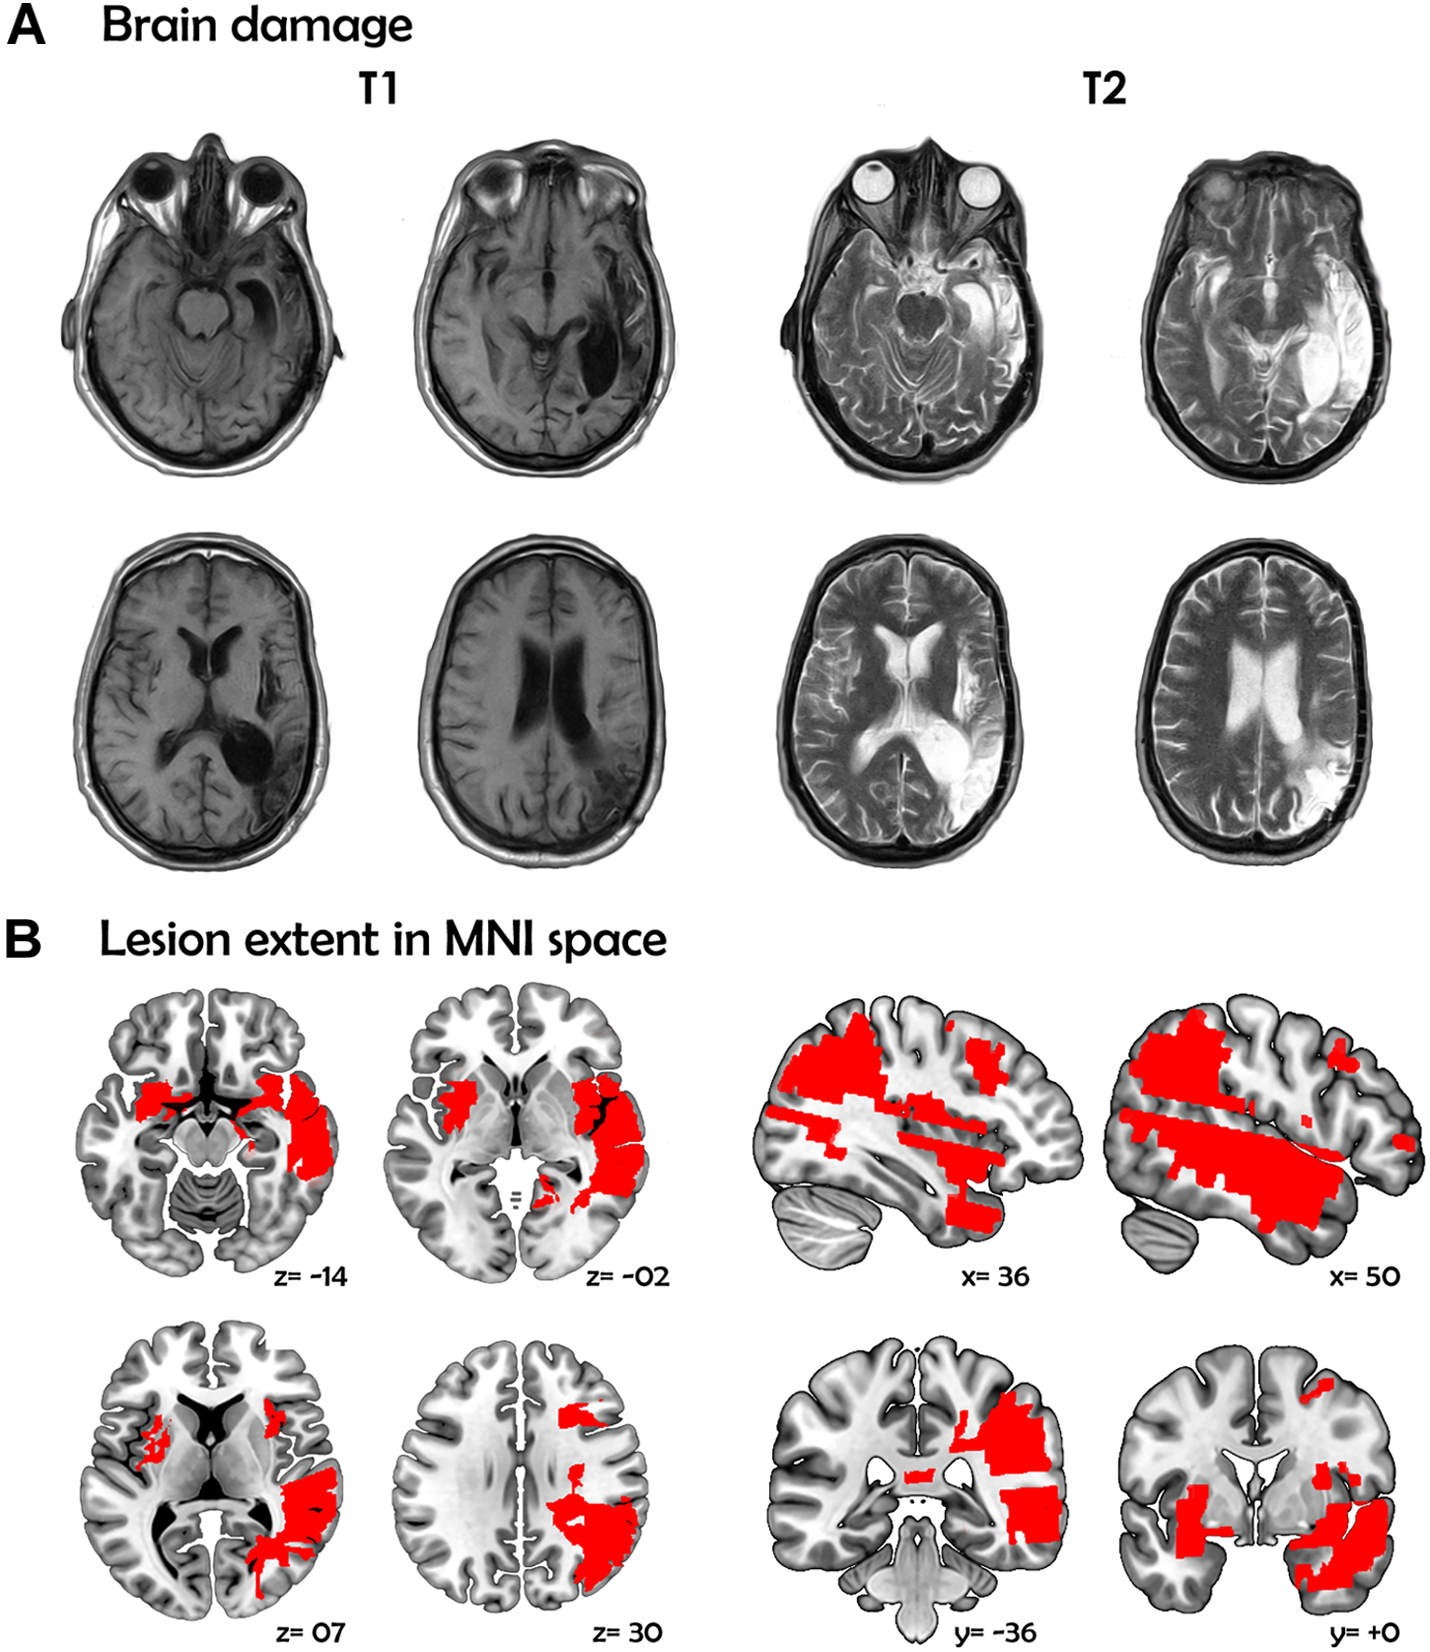

On September 9, 2011, at the age of 43, CG suffered from sudden severe headache, nausea, and loss of consciousness. During hospitalization, radiological findings revealed a subarachnoid hemorrhage (Fisher scale: grade IV; Hunt-Hess scale: grade V) due to a ruptured 5-mm fusiform aneurysm at the right medial cerebral artery which later complicated with severe vasospasm, leading to extensive damage affecting multiple RH regions, namely: the medial anterior temporal lobe (parahippocampal gyrus and amygdala), the mid and superior temporal gyri, the supramarginal and angular gyri, the inferior parietal lobule, the complete insula, a portion of the putamen, and the inferior frontal operculum (Figure 1; for details on the extension of the lesion in each area and additional images highlighting the involvement of the left and right amygdala, see Supplementary Material). Of note, such regions have been previously related to inferencing (Martin and McDonald, 2005, 2006), prosody production (Blumstein and Cooper, 1974; Bryan, 1989; Dykstra et al., 1995), and non-literal language comprehension (Martin and McDonald, 2005; Côté et al., 2007; Martín-Rodríguez and León-Carrión, 2010). She spent 41 days in intensive care and was then discharged with moderate left-sided hemiparesis.

MRI scans and lesion extent of patient CG. (A) Brain damage. T1 and T2 image showing axial views of the patient’s brain. (B) Lesion extent in MNI space. Multislice overlap of lesions within a normalized brain from the MNI brain atlas. On the right hemisphere, these included the fronto-insulo-temporal cortices, spanning from the medial anterior temporal lobe (parahippocampal gyrus and amygdala) to the mid and superior temporal gyri; the supramarginal and angular gyri; the inferior parietal lobule; almost the complete insula; and a portion of the putamen and the inferior frontal operculum. On the left hemisphere, compromised regions included the left anterior insula and its underlying white matter, the putamen, and the dorso-lateral amygdala. All images are in neurological orientation.

Two years later, a second (ischemic) stroke produced by a sudden reswallowing (presumably related to a previous craniotomy) induced additional damage in the LH, including the anterior insula and its underlying white matter, the putamen, and the dorso-lateral amygdala (Figure 1). These regions have been implicated in bilingual processing via phonological (Klein et al., 1994; Chee et al., 2004; Tettamanti et al., 2005; Abutalebi et al., 2013), semantic (Copland et al., 2002; Wartenburger et al., 2003) and syntactic (Tschirren et al., 2011; Park et al., 2012; Hernandez et al., 2015) tasks.